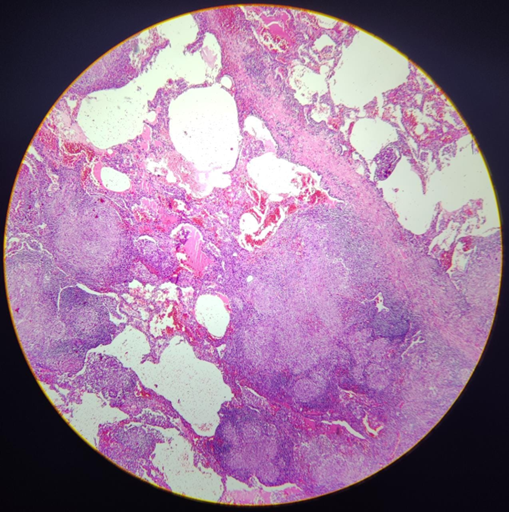

Órgão: Pulmão

Descrição: Corte de pulmão com a presença de processo inflamatório crônico granulomatoso caracterizado pela presença de centro de necrose caseosa, circundado por macrófagos epitelióides, células gigantes multinucleadas do tipo Langhans e halo linfocitário. Nota-se ainda área de fibrose.

Diagnóstico: Tuberculose (inflamação crônica granulomatosa do parênquima pulmonar).